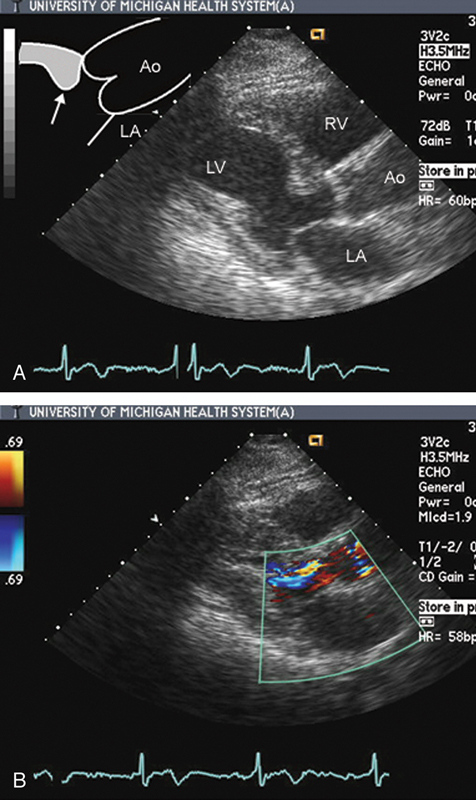

فحوصات تشخيصية لبعض امراض القلب والشرايين التاجية